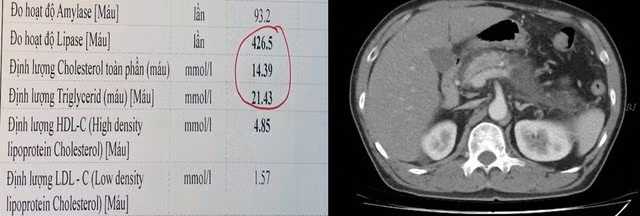

Kết quả xét nghiệm cho thấy men tuỵ và mỡ máu tăng rất cao, gấp khoảng 12 lần giới hạn bình thường (Cholesterol 14,3 mmol/L, Triglycerid 21,43 mmol/L). Hình ảnh chụp CT ổ bụng ghi nhận tổn thương tuỵ nặng, thâm nhiễm và có tụ dịch quanh tuyến tuỵ, biểu hiện của viêm tuỵ cấp mức độ nặng, thâm nhiễm kèm tụ dịch xung quanh.

Kết quả xét nghiệm mỡ máu tăng rất cao (trái) và hình ảnh tổn thương viêm tụy cấp mức độ nặng trên phim CT ổ bụng của bệnh nhân (phải). Ảnh SKĐS